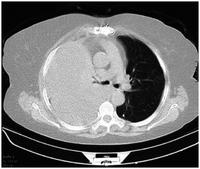

Computed tomography (CT or CAT) scans may be useful for diagnosing retained hemothorax as this form of imaging can detect much smaller amounts of fluid than a plain chest X-ray. However, CT is less used as a primary means of diagnosis within the trauma setting, as these scans require a critically ill person to be transported to a scanner, are slower, and require the subject to remain supine.[23][26]